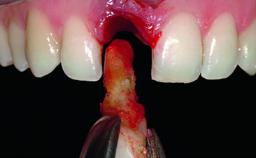

Replacement of a Compromised Upper Right Central Incisor: Hard- and Soft-tissue Augmentation, Late Placement of an RC Bone Level Implant

A 36-year-old male patient with a compromised maxillary central incisor was referred by his general dentist for consultation. The patient’s chief complaints were the gradual debonding of a temporary crown on the right central incisor and unsatisfactory esthetics due to an increasing diastema between the right central and lateral incisors. The patient reported a traumatic event some years previously, when a crown had been placed after root-canal treatment. The referring dentist wanted to provide a new crown restoration, but was concerned about the condition of the residual root. Anamnesis was negative for any other dental or periodontal pathology in the remaining dentition. The patient reported taking no medications: He was a smoker (10 to 15 cigs/day) and had realistic esthetic expectations.

Bone Volume Deficient horizontally, requiring prior grafting